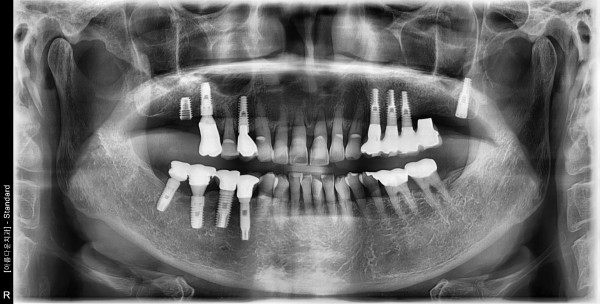

78세 여자 상하악 구치부 뼈 이식후 임플란트 식립